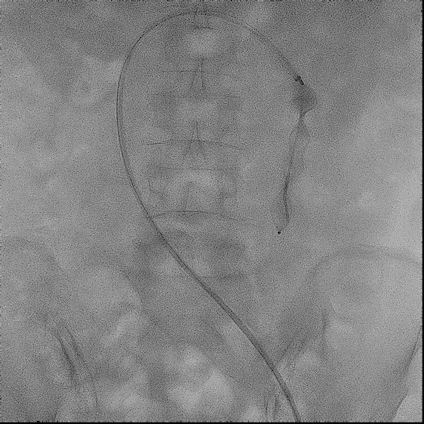

手术过程(一):

右股静脉穿刺,交换8 F-90 cm长鞘导入A3段,造影见A3段远端显影良好,中段动静脉瘘高速血流,可见“瘤槽”显影。

图片图片